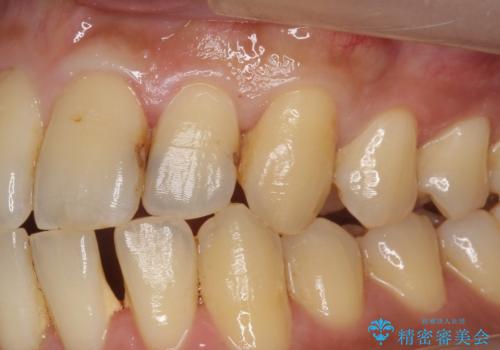

ジルコニアクラウンについて

ジルコニアクラウンは表面がツルツルして

汚れ(細菌)や着色がつきにくいです。

ジルコニアクラウンスペシャルはジルコニアクラウンスタンダードに比べ

色のバリエーションが多く、よりご自身の天然歯の色と合うように作れます。

自然な被せ物が入り、大変満足して頂けました。